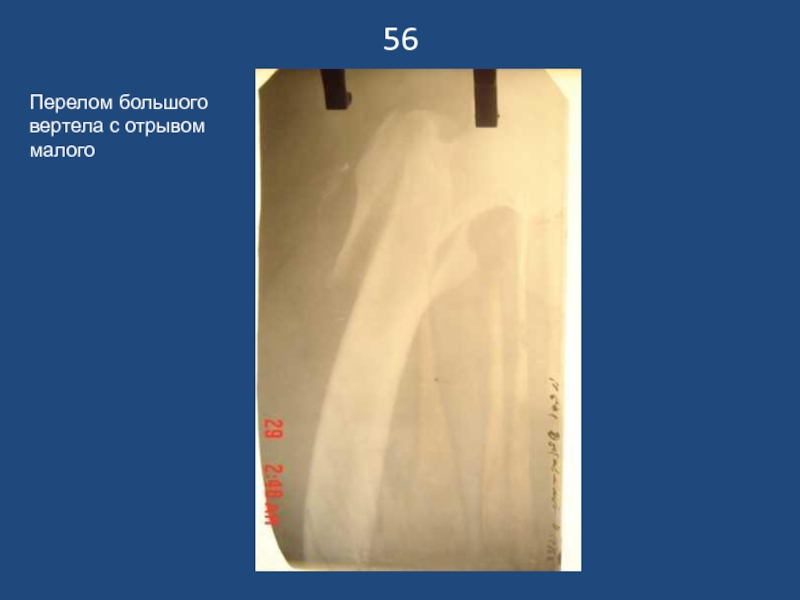

Перелом большого вертела с отрывом малого

56Перелом большого вертела с отрывом малого